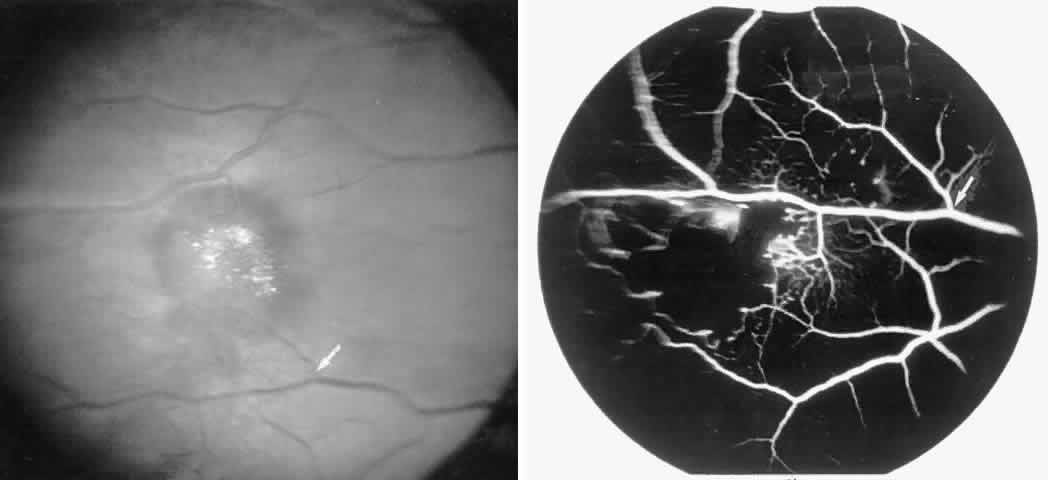

Disc Sign

Transient dark red spots (similar to conjunctival commas), representing plugs of sickled erythrocytes within superficial capillaries, may be seen on the surface of the optic disc (Fig. 3 and Color Plate 1A). These disc changes are not associated with any functional or anatomic abnormalities. They are found in 11% of all patients with sickle cell disease, but appear to be more common in patients with homozygous sickle cell anemia, occurring in 29% of these patients.67 The disc sign correlates with the presence of conjunctival commas and ISCs.

Vascular Tortuosity

Dilation and tortuosity of the retinal veins was one of the first recognized abnormalities of sickle cell eye disease. Although it is not pathognomonic of sickle cell disease, it reportedly occurs in up to 47% of patients with homozygous sickle cell anemia and 32% of patients with SC disease (Fig. 4).70 The significance of this venous tortuosity is unknown, and the incidence does not appear to be related to age.71

Angioid Streaks

Angioid streaks occur in association with sickle cell disease, with an overall incidence of less than 6%.72–75 The changes are more common in patients with homozygous sickle cell anemia and are age-dependent, occurring in 2% of sickle cell anemia patients less than 40 years of age versus 22% in those who are more than 40 years of age (Fig. 5).76